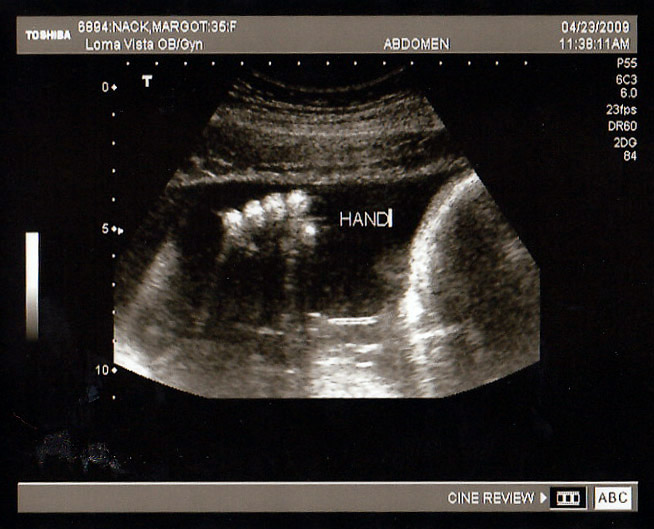

John & Margot Nack